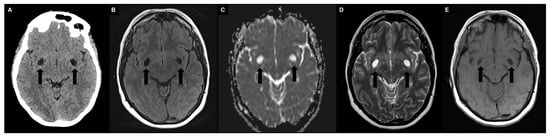

| Features | PVS | Subcortical Infarct | Lacune | WMH | Giant PVS | Benign Intracranial Cysts | Neoplastic Intracranial Cysts | Vascular and Inflammatory Cysts | Infectious Cysts | Mucopolysaccharidosis |

|---|---|---|---|---|---|---|---|---|---|---|

| FLAIR | ↓↓ | ↑↑ | ↓↓ with ↑ rim | ↑↑ | ↓↓ with ↑ rim | ↓↓ (↑ in neurenteric cysts) | ↑↑with possible ↑ rim | ↓↓ with ↑ rim | Variable | ↓↓ with ↑ rim |

| T2 | ↑↑ | ↑↑ | ↑↑ | ↑ | ↑↑ | ↑↑ | ↑/↑↑ | ↑↑ | Variable | ↑↑ |

| T1 | ↓↓ | ↓↓ | ↓↓ | ↓ | ↓↓ | ↓↓ (↑ in neurenteric cysts) | ↓/↓↓ | ↓↓ | Variable | ↓↓ |

| Enhancement | - | - | - | - | - | - | ↑ of solid tissue | ↑ in active inflammation | Variable (eccentric target sign for neurotoxoplasmosis, cyst wall for neurocysticercosis) | - |

| DWI | - | Restricted | - | - | - | Restricted in epidermoid cyst | Restricted | - | Restricted in cryptococcosis | - |

| Size | ≤2 mm | ≤20 mm | 3–15 mm | ≥3 mm | ≥15 mm | ≥15 mm | ≥15 mm | ≥3 mm | ≥15 mm | ≥3 mm |

| Shape | Dot-like or tubular | Dot-like or tubular | Wedge | Rounded or irregular | Bizarre cystic configurations | Rounded | Bizarre cystic configurations (“bubbly” for DNET) | Bizarre in encephalomalacia, linear or ovoid in multiple sclerosis | Rounded or irregular | Dot-like or tubular |

| Location | Symmetric in white matter or lower basal ganglia | Subcortical territory of a perforating arteriole | Asymmetric in white matter or upper basal ganglia | Symmetric in periventricular white matter | Mesencephalothalamic region (type III), anterior superior temporal lobe (type IV) | Single intra-axial, subarachnoid or intraventricular | Single intra-axial | Encephalomalacia have connections with the subarachnoid space; perivenular distribution in multiple sclerosis | Multiple intra-axials, subarachnoids or intraventriculars | Basal ganglia, corpus callosum, and white matter |

| Other | - | - | - | - | - | - | Change in follow up | Clinical picture | Clinical picture | Clinical picture |